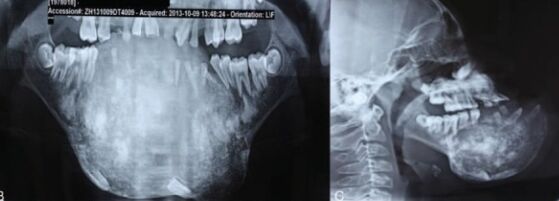

66.17歲男孩因上顎右側有一個無疼痛的腫脹而來求診,經X光檢查(如附圖)發現一個放射線不透過性影像如 箭頭所示之區域,根尖片可見到此病變與周圍界線不清楚,此病患最可能罹患下列何種疾病?

(A)家族性巨大畸形牙骨質瘤(familial gigantiform cementoma)

(B)繁盛性牙骨質骨發育不良(florid cemento-osseous dysplasia)

(C)纖維性發育不良(fibrous dysplasia)

(D)骨化纖維瘤(ossifying fibroma)

統計: A(127), B(94), C(780), D(137), E(0) #2625181